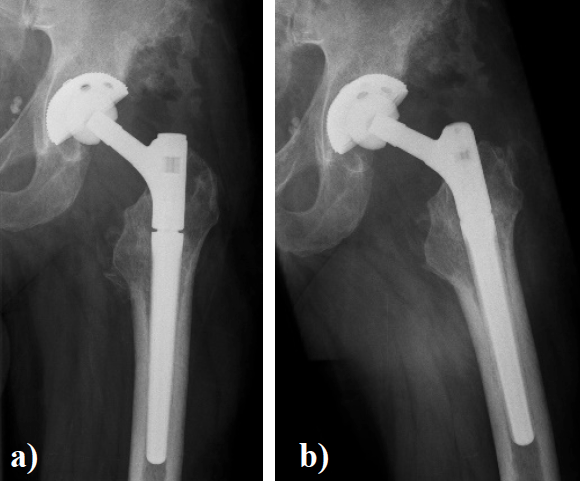

In August 2013 THA was performed due to a girdlestone situation after septic osteoarthritis of the hip (Figure 1) in a 46 year old male patient using a MRP Titan revision stem (Diameter: 18mm, length: 140 mm) (Peter Brehm GmbH, Weisendorf, Germany) and a cementless cup (Allofit - IT; Diameter 54 mm, Zimmer, Warsaw, USA) and a ceramic on ceramic bearing (head diameter: 36 mm) (Figure 2). The patient was 175 cm tall and weighed 105 kg (body mass index: 34.3 Kg/ m2). 2 weeks later revision surgery due to recurrent dislocation (Figure 3) was performed. Revision of the acetabular component was done using an Allofit - Classic- cup, Diameter 56 mm (Zimmer, Warsaw, USA)). The neck component was exchanged from small to medium size (Figure 4). A ceramic on PE bearing was implanted (head diameter: 32 mm). Postoperative healing was uneventful. The patient was out of any complaints. In February 2016 the patient started suffering from slight thigh pain but detected crepitation in the region of the left hip. X-ray of the left hip in 2 planes in May 2016 revealed an asymmetrically gap of the stem / neck junction (Figure 5). During revision surgery of the left hip breakage of the cone of the morse taper junction was visible (Figure 6). Removal of the well-fixed stem was performed via a distal fenestration. After fixation with cerclage wires a bended MRP Titan revision stem (Diameter: 19 mm, Length: 200mm with long neck and extension sleeve) was implanted using a 32 mm ceramic head (Figure 7). Postoperative healing was uneventful.

Figure 3. X - ray of the left hip (ap view) shows dislocation of the left hip.